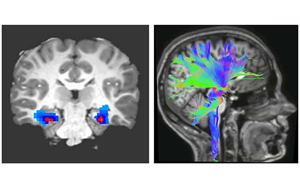

Nature Medicine:一種新的強迫癥神經(jīng)生物標(biāo)志物

貝勒醫(yī)學(xué)院和德克薩斯兒童醫(yī)院最近的一項研究確定了一種特定的神經(jīng)活動模式,作為一種新的生物標(biāo)志物,可以準(zhǔn)確預(yù)測和監(jiān)測接受深部腦刺激(DBS)治療的強迫癥(OCD)患者的臨床狀態(tài),深部腦刺激是一種迅速出現(xiàn)的治療嚴(yán)重精神疾病的方法。